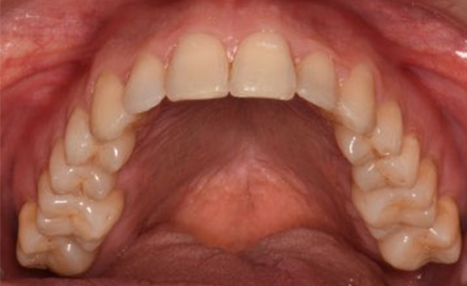

A 38-year-old male patient sought orthodontic treatment with both functional and esthetic concerns. His main complaints included the appearance of an inverted smile arc, reduced incisor display, and a general lack of harmony in his smile.

The extraoral examination revealed a long facial type with an increased lower facial third, nasolabial folds accentuated by insufficient midface support, and broad buccal corridors due to maxillary compression. Intraoral analysis showed a posterior crossbite, negative torque on posterior teeth, and an altered occlusal balance. Radiographic and cephalometric evaluation confirmed the clinical findings, with an increased mandibularplane angle and mandibular posterior rotation. This rotation contributed to a convexity of +4 mm, although the underlying problem was a retruded maxilla with insufficient midface support. Vertical facial height was also increased. Importantly, the temporomandibular joint evaluation showed a posterior condylar position with intact cortical bone, no pain, and no joint sounds.

(Images: Intraoral Initial)